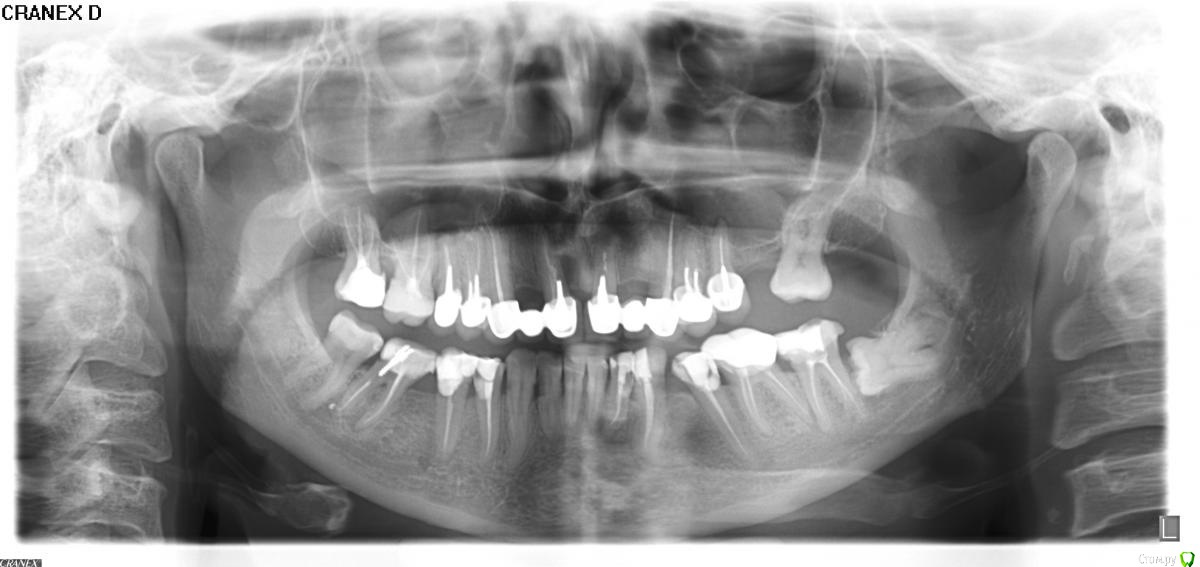

Svettala Опубликовано 11 апреля, 2016 Поделиться Опубликовано 11 апреля, 2016 (изменено) Добрый день. Назрел вопрос по имплантации передних верхних зубов, посетила нескольких клиник и мнения расходятся. Хотелось бы по максимуму сохранить свои зубы, 11 и 21 под удаление (11 - резекция 30 лет назад, 21 - периодически свищ), 12 и 22 удалены давно. На 25 киста и тоже надо удалять. Теперь самое интересное: один доктор говорит, что также надо удалять и 26, тогда придется делать синус-лифтинг, но можно не трогать 48, другой доктор предложил удалить кроме единиц еще и 24, 25, 14, 15, 48,47 (26 без вопросов-норм). Хотелось бы поставить импланты только на 12 и 22 с подсадкой костной ткани (если , конечно, возможно) и может быть еще на 25, с остальными зубами пока не готова расставаться, тем более они меня вообще никак не беспокоят и не беспокоили, но коронки на них заменить хочу. Мне 45 лет и хочется надеяться, что и 8 так и «забудет» про меня и я про него. Снимок получше, если надо, смогу выложить позже. Изменено 11 апреля, 2016 пользователем Svettala Ссылка на комментарий

Bier Опубликовано 11 апреля, 2016 Поделиться Опубликовано 11 апреля, 2016 для принятия решения по 25,26,14,15 зубам необходимо снять с них коронки, вынуть штифты и посмотреть что останется от зуба. Если зуб будет пригоден к восстановлению, то пролечить каналы и сделать новые коронки.48 - удалять.47 - можно сохранить. Ссылка на комментарий

Svettala Опубликовано 11 апреля, 2016 Автор Поделиться Опубликовано 11 апреля, 2016 (изменено) Спасибо за ответ, а проблемно ли вытаскивать штифты, если он обломится то зуб 100% под удаление? Снимок, к сожалению, перевернут, восьмерка у меня слева. Изменено 11 апреля, 2016 пользователем Svettala Ссылка на комментарий